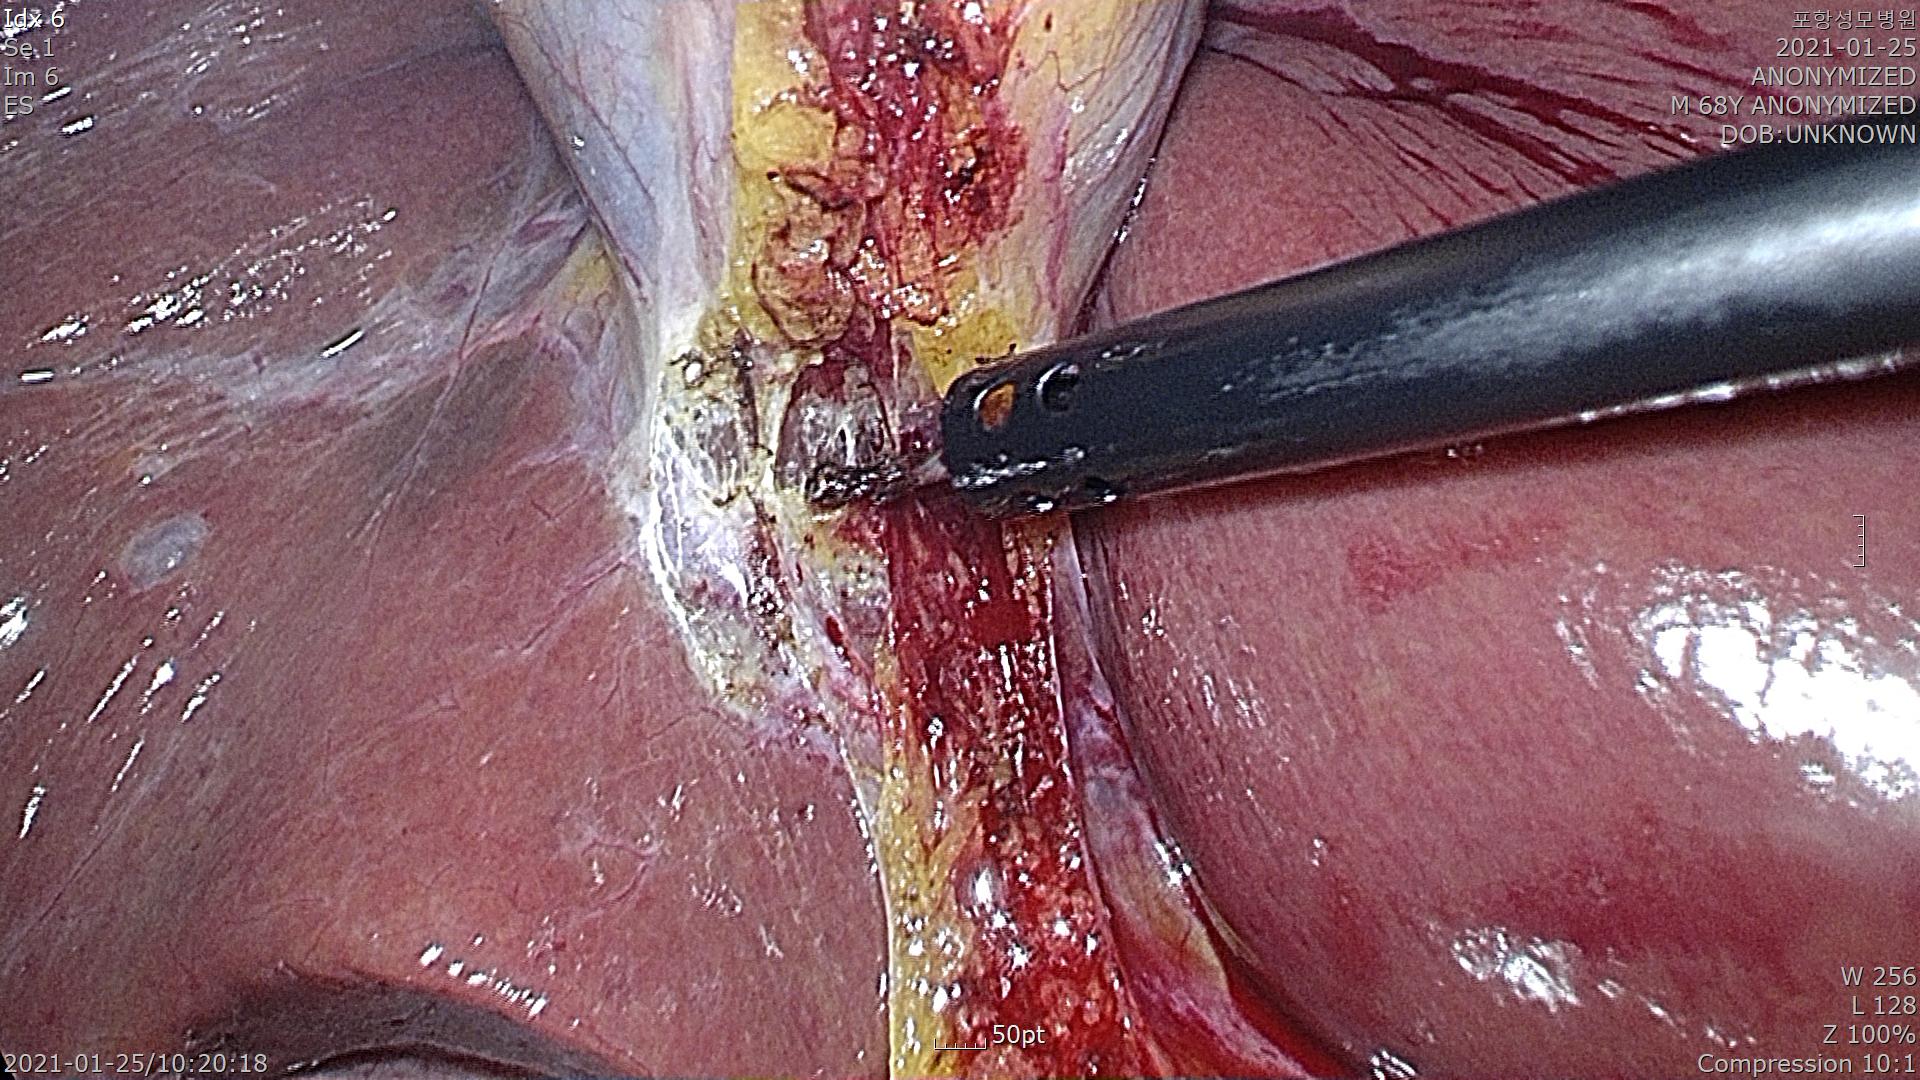

담낭이 보이고 총담관이 잘 확인됩니다.

담낭관을 확인하고 박리합니다. 결찰을 3번 합니다.

담낭관을 절제하고 간후벽에서 담낭을 제거합니다.

담낭을 잘 제거하고 담낭안에 있는 담석을 확인했습니다.

수술은 합병증 없이 잘 끝났습니다.

수술은 20분 걸렸습니다.